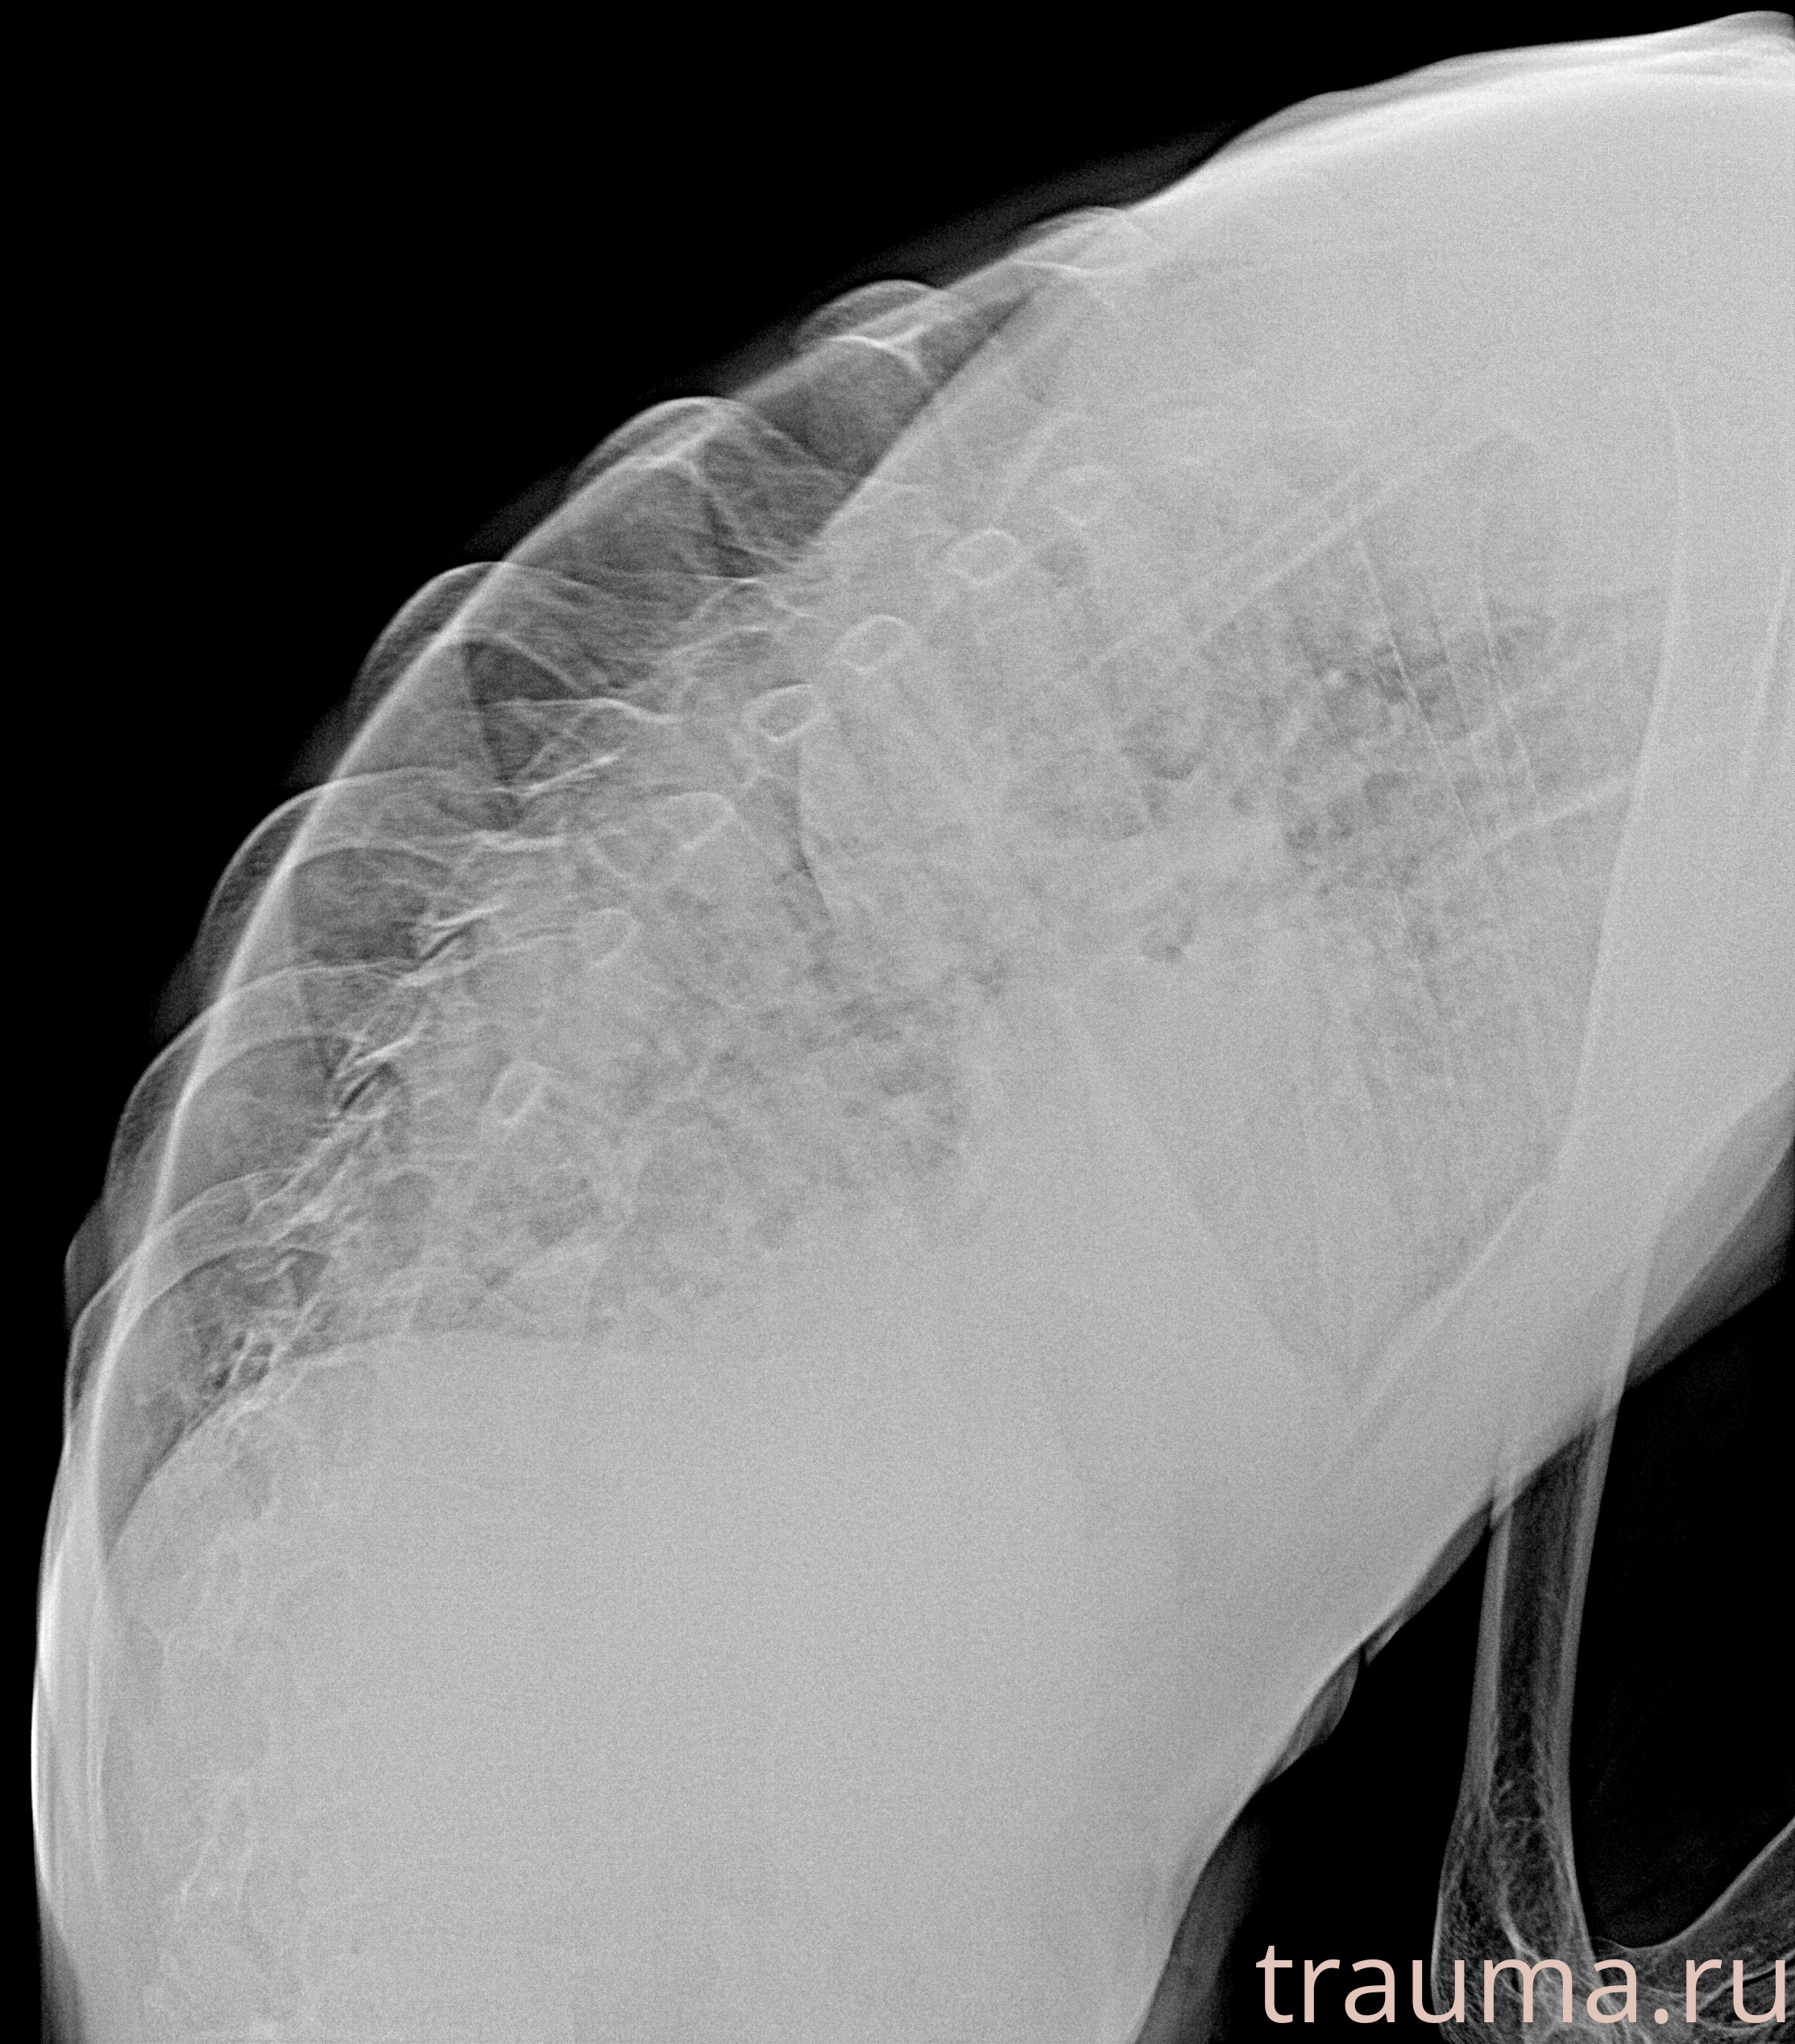

Рентген на дому: по вашему адресу приезжает врач-рентгенолог, травматолог-ортопед с мобильным рентгеновским аппаратом, проводит диагностику травмы или заболевания, делает необходимые рентгенограммы, дает рекомендации по дальнейшему лечению. Получить качественные снимки в домашних условиях возможно благодаря уникальной методике, разработанной МосРентген Центром для института  Склифосовского